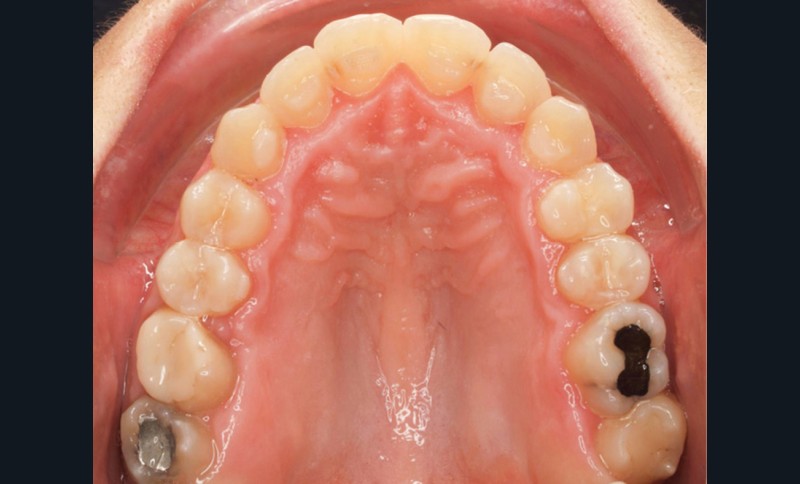

Diagnostic (fig. 1a-g)

La patiente présente une classe III squelettique dans un contexte hyperdivergent associée à une endoalvéolie maxillaire, un articulé inversé antérieur, une rétroversion incisive maxillaire, des rapports de classe I canine bilatérale, une absence de 16 et 36.

Le sourire est étroit, dégradé par les malpositions dentaires.